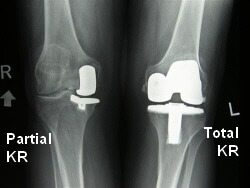

A partial knee replacement is a type of knee surgery where half of the knee joint is removed and replaced with a metal and plastic prosthesis.

Partial knee replacements are performed when there is damage to one side of the knee joint, usually from arthritis. Partial knee replacements are also known as a Uni Knee Replacement (UKR), Unicompartmental Knee Arthroplasty or PKR.

In the past, the operation of choice for knee arthritis was a total knee replacement (TKR).

This was the case whether the arthritis affected the whole knee, or just part of the knee. This meant that any healthy part of the knee joint had to be removed alongside the part affected with arthritis.

The development of partial knee replacements means that now, if arthritis is confined to only one side of the knee, that side can be replaced and the healthy bone, cartilage and ligaments do not have to undergo unnecessary surgery.

Partial knee replacement surgery itself is quicker, there is less damage to the knee, the cruciate ligaments are preserved and there are less complications than with a total knee replacement.